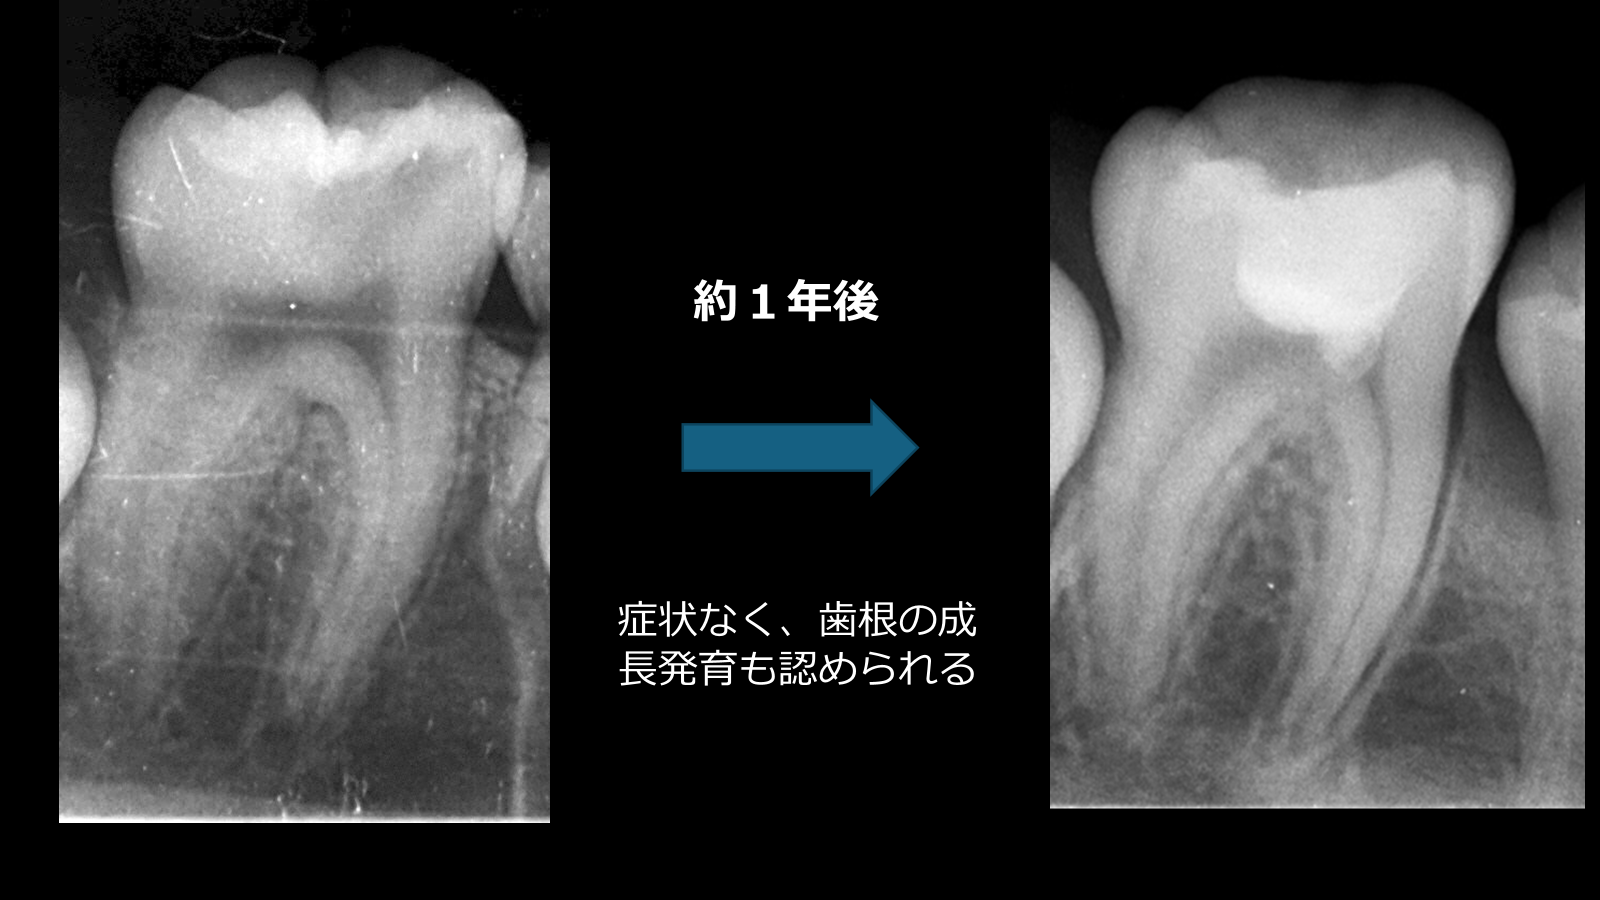

術後は定期的に経過観察を行い、

6か月後および約1年後のレントゲンにて

症状なし

EPT(+)

歯根の成長を確認

歯髄の生活反応および歯根発育を認め、良好な経過を示している。